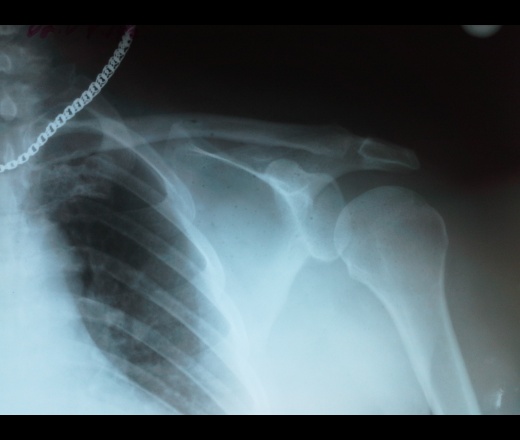

Рис. 1. Артрит (гнойный) правого локтевого сустава. Рентгеновская суставная щель неравномерно сужена, в медиальном отделе - расширена за счет деструкции суставной замыкательной пластинки и субхондрального слоя локтевой кости, в этом месте - мелкие внутрисуставные секвестры; регионарный остеопороз.

Рис. 2. Деформирующий артроз правого плечевого сустава. Рентгеновская суставная щель равномерно сужена на всем протяжении, замыкательные пластинки уплотнены, в субхондральном слое - остеосклероз, в краевых отделах - костные разрастания.